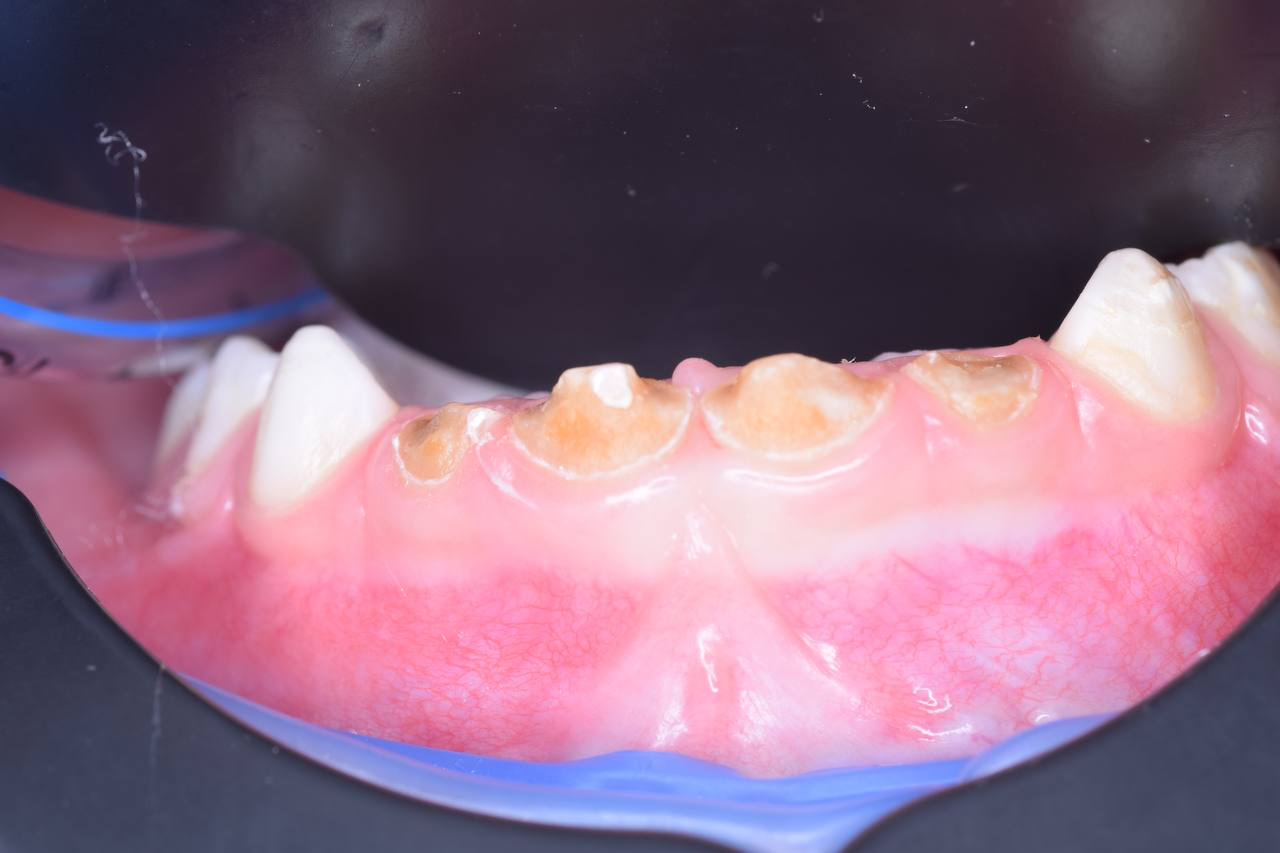

Большое внимание уделяет профилактике и обучению индивидуальной гигиене детей и их родителей.

С самого начала профессиональной деятельности знала, что детские зубы и искренние улыбки ничем не заменить.